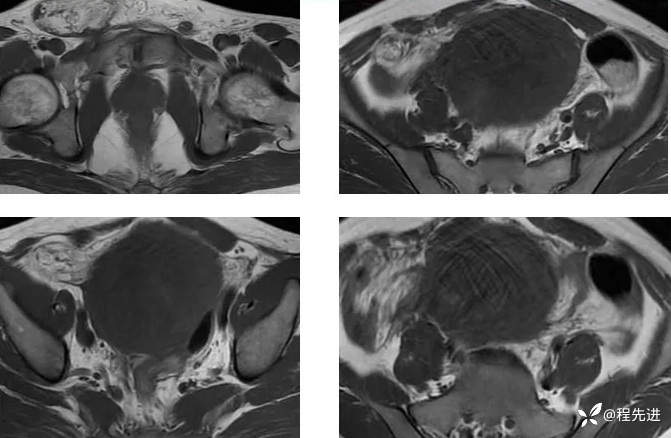

【腹盆】特别精彩病例|下腹痛20余天,男性病人腹腔巨大肿块该如何诊断

【患者信息】:男,41岁

【主诉】:下腹痛20余天

既往史:隐睾

肿瘤标志物:甲胎蛋白(AFP)>10000

增强: